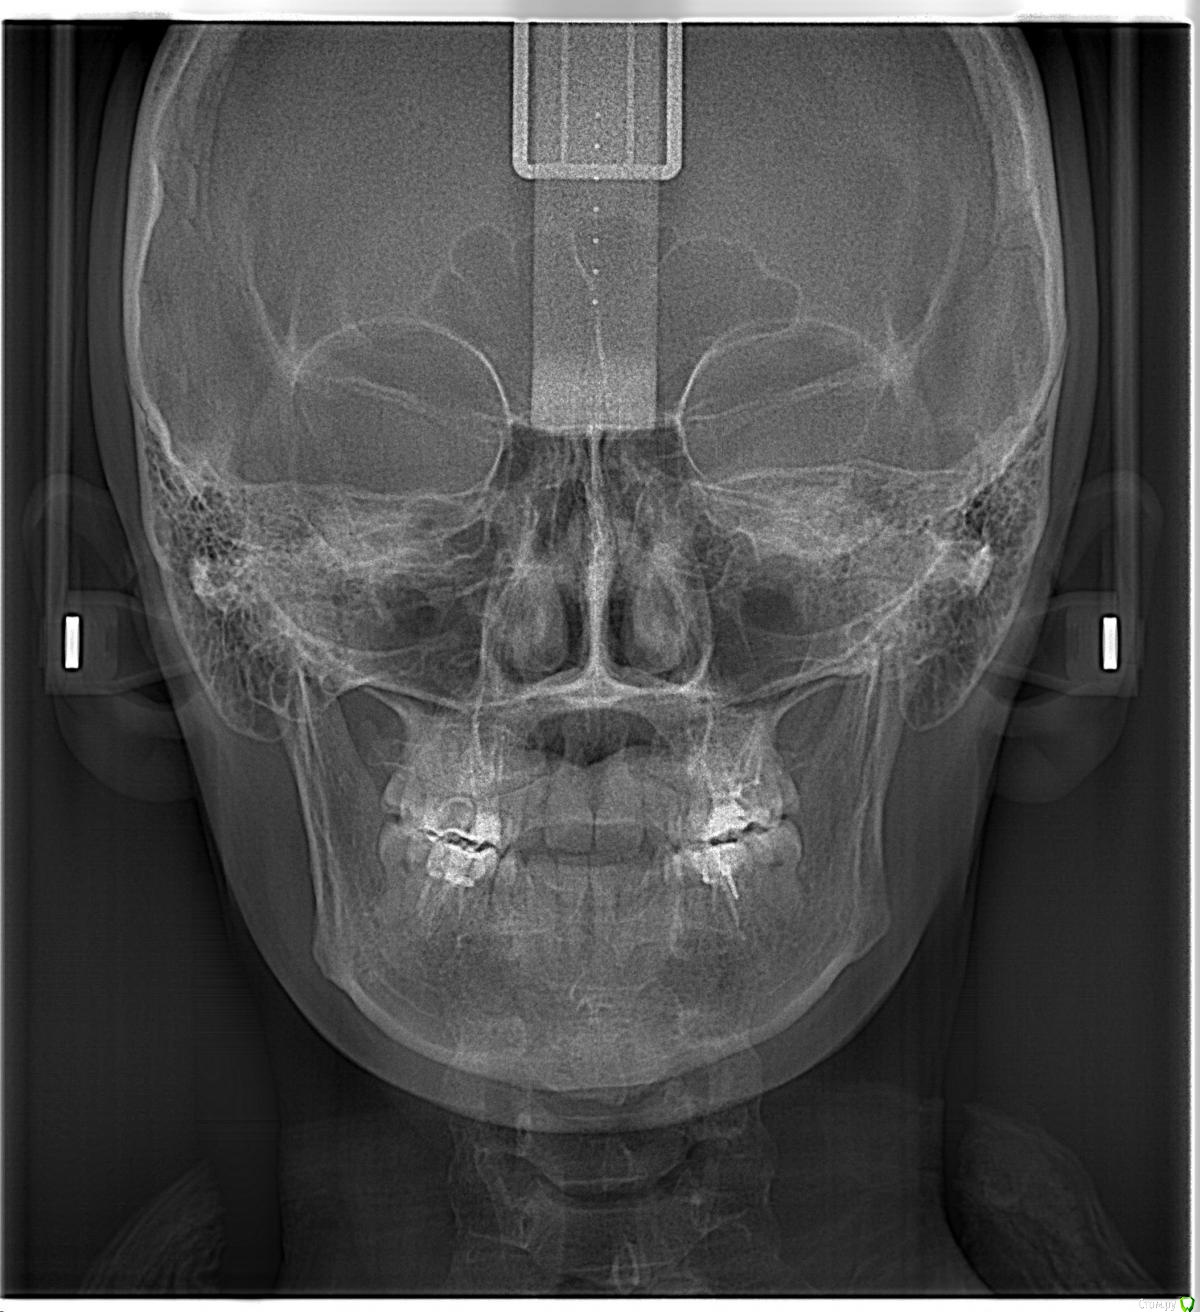

После лечения жевательных зубов на нижней и верхней челюсти начался дискомфорт в прикусе. Врач подшлифовал пломбы, начались боли в мышцах. Попробывал завысить, стало еще хуже. Через месяц начались щелчки с левой стороны, боли усиливались в районе жевательных мышц. Пробывали капы, результатов не давало. Сейчас не могу ни переживать толком еду, спать вообще не удобно. челюсть в обычном положении зафиксировать не могу, жевательных мышц совсем не чувсвую,разговаривать тоже не удобно, слюну ковтать трудно.Сильно напряжены мышцы возле носа, сзади головы и шеи, раслабить никак не могу. Начались сильные головные боли, боли в шее, в левой лопатке.  Сделали мрт шейного отдела, показало деформация шейного отдела и грыжи. Стоматологи говорят что это из-за прикуса. К кому обратиться помогите,Есть фотография до лечения, прикрепляю.

КТ даёт лишь информацию относительно костных структур сустава, а хотелось бы увидеть что там со связками, но для этого нужно МРТ. Со стороны костных структур я не увидел каких-то критических изменений, за исключением может быть ремоделирования суставных поверхностей.